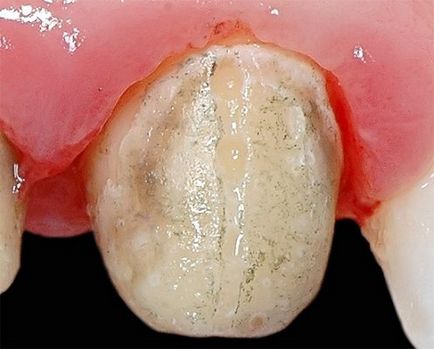

Зуб з карієсом без лікування стане причиною багатьох проблем

Каріозні зуби дуже непраівлекательние